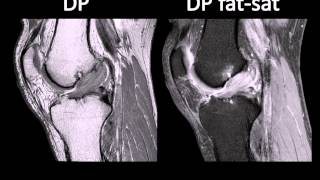

WebEl primer signo de rotura del LCP en RM es el engrosamiento difuso del trayecto ligamentoso en el plano sagital, midiendo 7 mm o más de espesor (3). En las roturas. WebDegeneración mucoide en Ligamento Cruzado Anterior (LCA) con hiperseñal y engrosamiento. Pequeño derrame articular. La verdad es que no estoy tampoco del todo. WebLigamento cruzado anterior mucoide: serie de casos y revisión bibliográfica Ligamento cruzado anterior mucoide: serie de casos y revisión bibliográfica / Mucoid degeneration. WebLa rotura del ligamento cruzado anterior (LCA) de la rodilla es una lesión ligamentosa frecuente, especialmente en la práctica deportiva, siendo el mecanismo más común de. WebDepende la clinica que tengas. Hay casos de degeneracion mucoide en los que hay deficit de flexión, causando dolor al intentar doblar a partir de ciertos grados. En estos casos. WebUna de las lesiones de rodilla más comunes es un esguince o desgarro del ligamento cruzado anterior (ACL). Los atletas que participan en deportes de alta demanda como el.